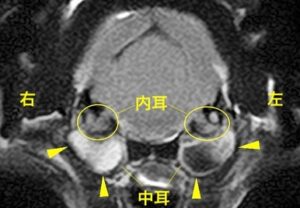

左右の鼓室胞内(内耳)の内腔を占拠する内容物を認める

診断名:両側の重度中耳炎・内耳炎